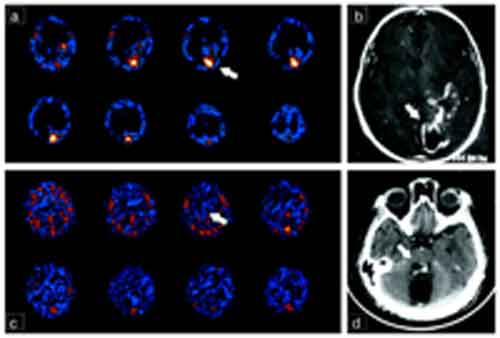

L’analisi genetica di un paziente turco il cui cervello manca delle caratteristiche circonvoluzioni cerebrali del cervello umano ha permesso di rivelare che la deformità era causata dalla delezione di due singole “lettere” in un gene, quello per la laminina gamma 3 (LAMC3), una mancanza riscontrata anche in due altri pazienti con un’anomalia analoga.

“Anche se lo stesso gene è presente in organismi inferiori con cervelli più lisci, come il topo, ne tempo si è in qualche modo evoluto acquistando nuove funzioni, che sono fondamentali per la formazione della corteccia occipitale umana e la sua mutazione porta alla perdita di superficie delle circonvoluzioni, una caratteristica del cervello umano”, ha detto Gunel.